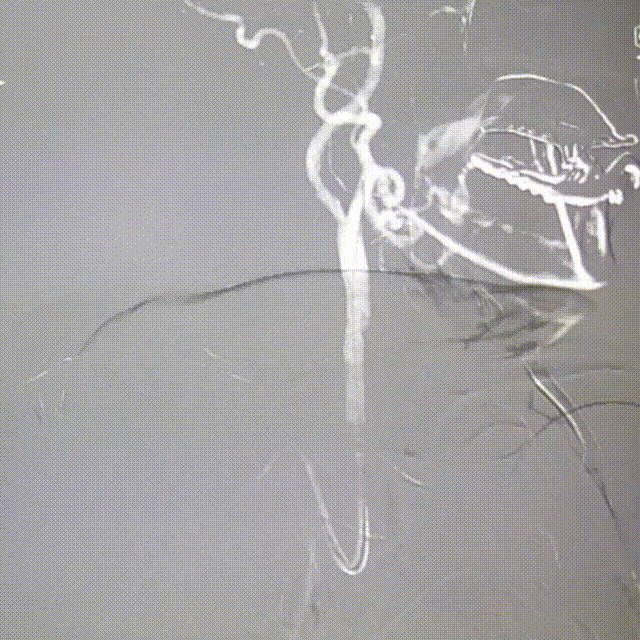

影像信息

右颈内造影